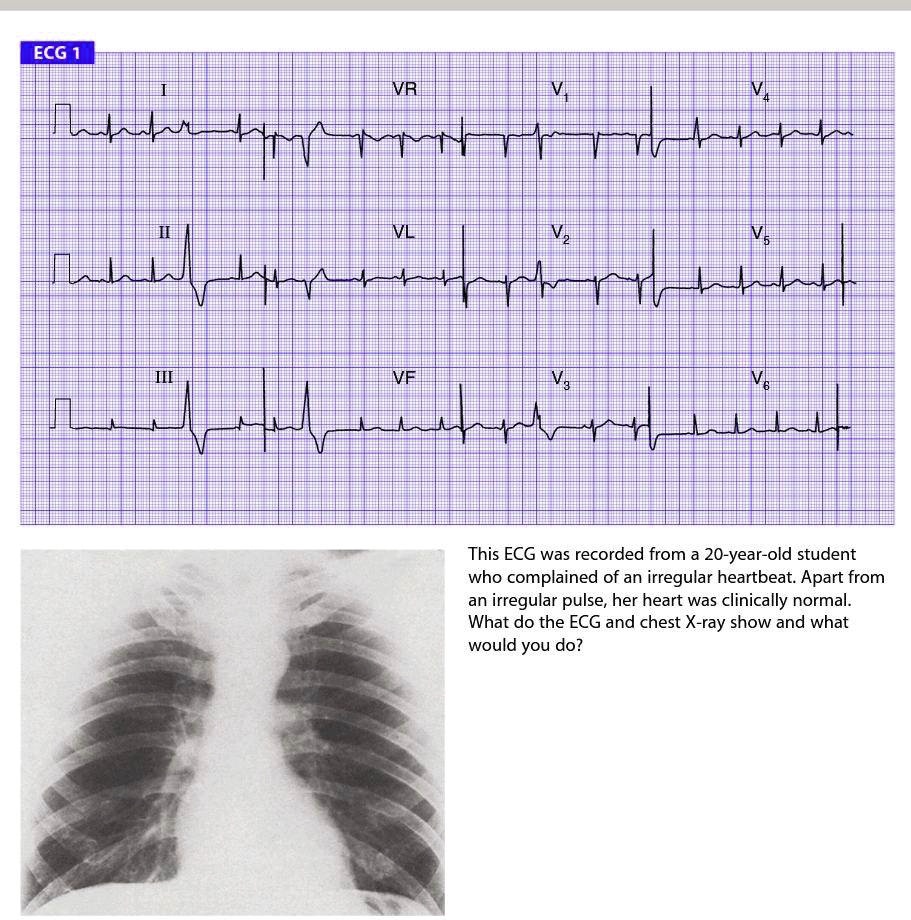

SOLVED ECG 1 VR This ECG was recorded from a 20yearold student who What Is Regular Irregular Heartbeat An irregular heartbeat (arrhythmia) is a change in the heart's beating pattern. Abnormal heart rhythms, or arrhythmia (also called irregular heartbeats), occur when the heart beats too fast, too slow, or. Learn the different types, causes, and effects. The main types of arrhythmia are: Heart arrhythmia treatment is usually only needed if the irregular heartbeat causes significant symptoms or puts. What Is Regular Irregular Heartbeat.